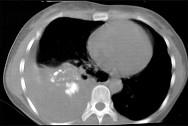

问题 男,66岁,剧烈胸痛,请结合CT图像,选择最可能的诊断 ( )

选项 A.右侧胸腔积液胸膜钙化 B.右肺癌侵犯胸膜 C.右侧胸膜间皮瘤 D.右侧肺不张 E.右侧肺肺癌

答案 C